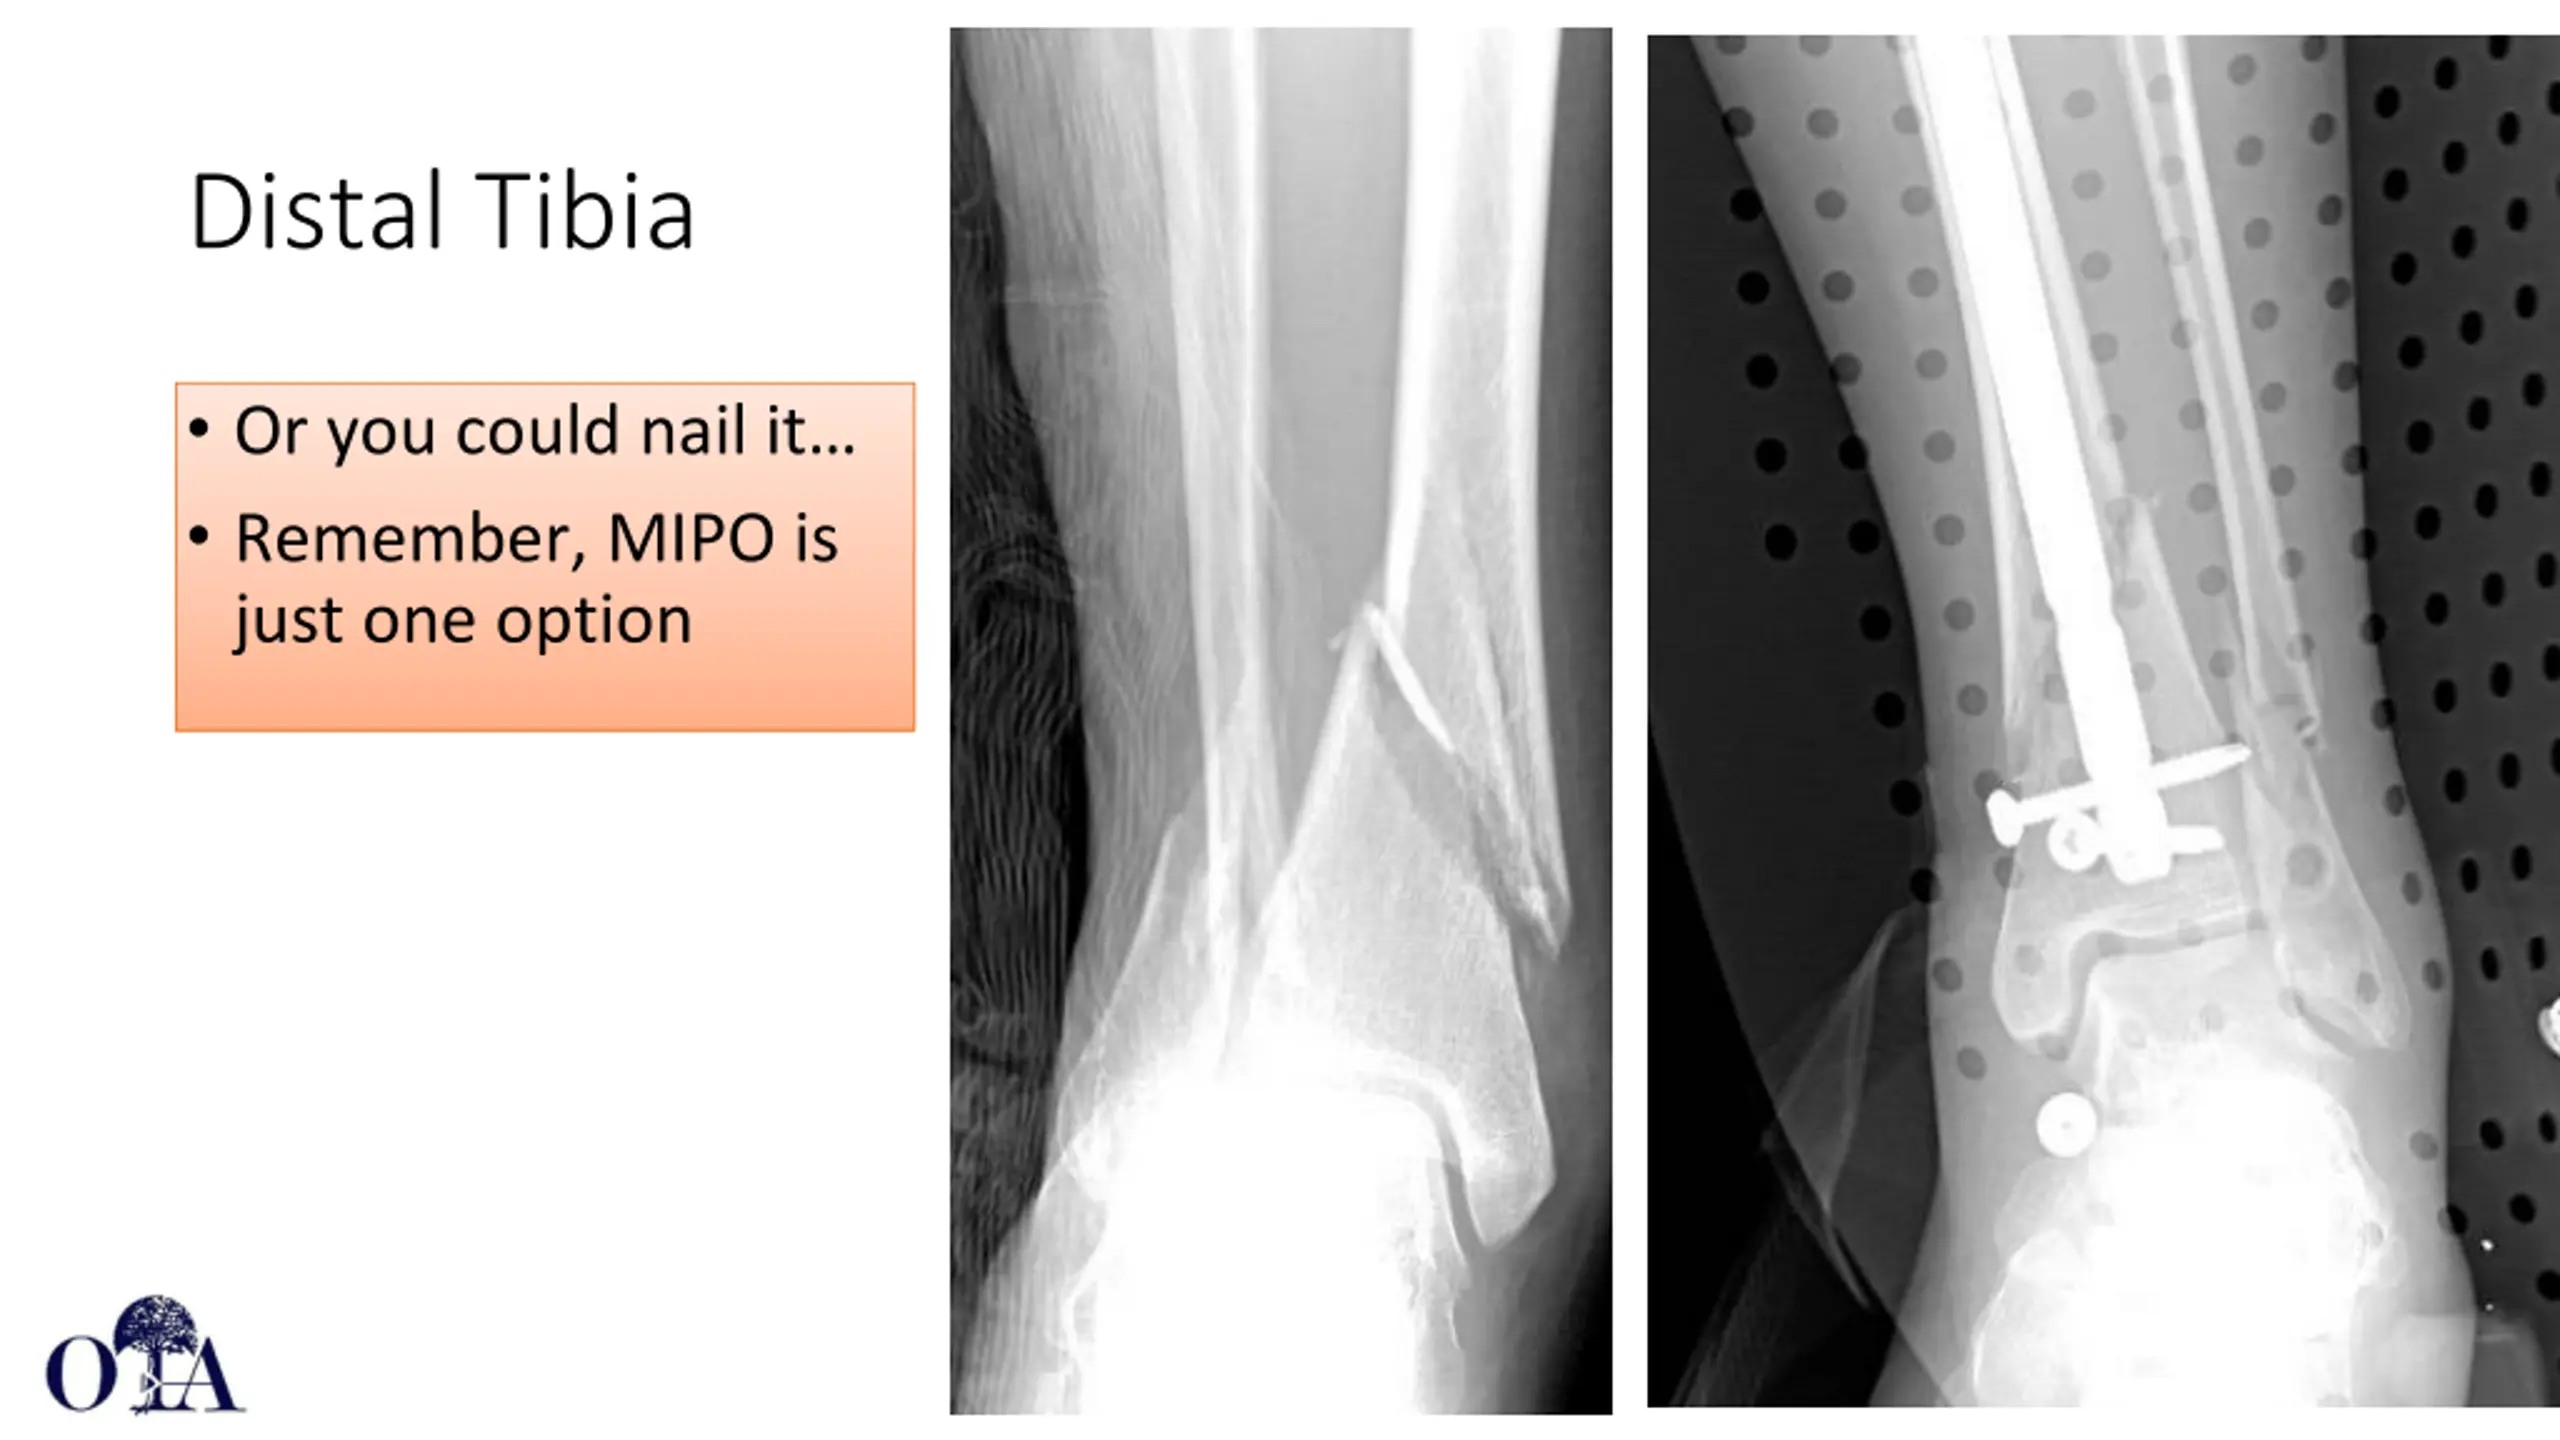

Distal Tibia Or you could nail it Remember, MIPO is just one option Core Curriculum V5